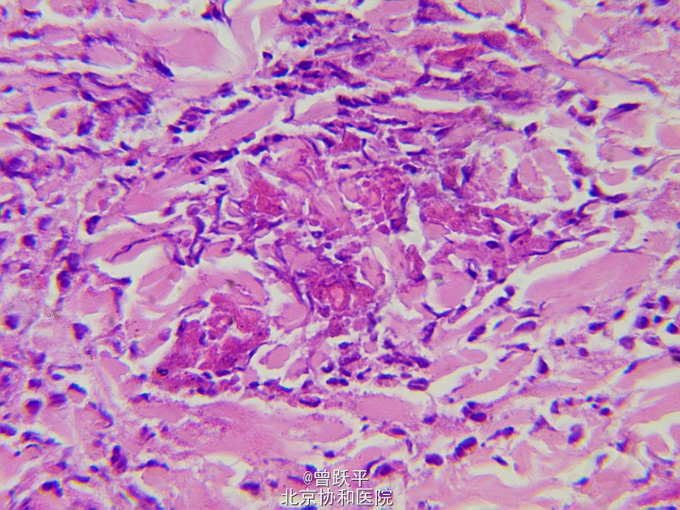

患儿女,5个半月。 因右手背皮肤结节、水疱、血疱,伴全身反复出现红斑、风团5个半月来我院就诊。 患儿出生时,右手小指掌指关节伸侧有一绿豆大丘疹,摩擦后肿大,表面起水疱、大疱或血疱,皮损渐增大。 患儿常出现全身阵发性红斑、风团和面色苍白,持续约数小时至数天后缓慢消退。 个人史:患儿系第一胎第一产,足月顺产。 家族中无类似患者。

查体:一般情况良好。系统检查无异常。全身浅表淋巴结未触及。 右手小指掌指关节伸侧可见一1.4cm×2.5cm棕红色结节,界清,橡皮样硬度。 躯干、四肢散在分布许多大小和形态不一的红斑和风团

单发性肥大细胞瘤 口服氯苯那敏2mg/d,红斑和风团明显减少,此后右手背皮损逐渐变小。

患儿6岁时随访,皮损已完全消退。